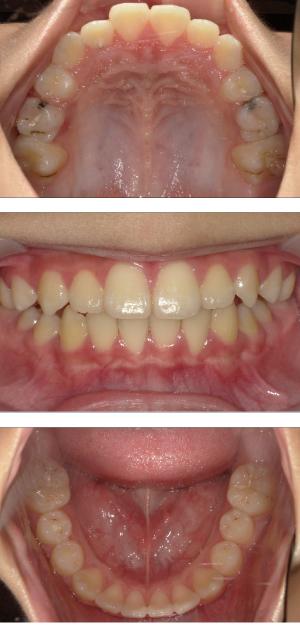

バイオブロック矯正(顎顔面口腔育成治療)

矯正治療は大人になって始めるよりも子どもの頃から始めた方が確実に良い結果をもたらします。成長が盛んな子供の時期に、顎や顔の成長を利用しながら治療ができる大きなメリットがあるからです。当院では、非抜歯矯正を推奨しておりバイオブロック矯正を取り入れています。

バイオブロック矯正の考え方は歯並びが悪くなる原因にアプローチする治療法になります。

舌の位置や口呼吸から乱れてしまった下顎の後退を正し、顎顔面が本来あるべき位置へと誘導させていく治療です。

- 歯並びの改善